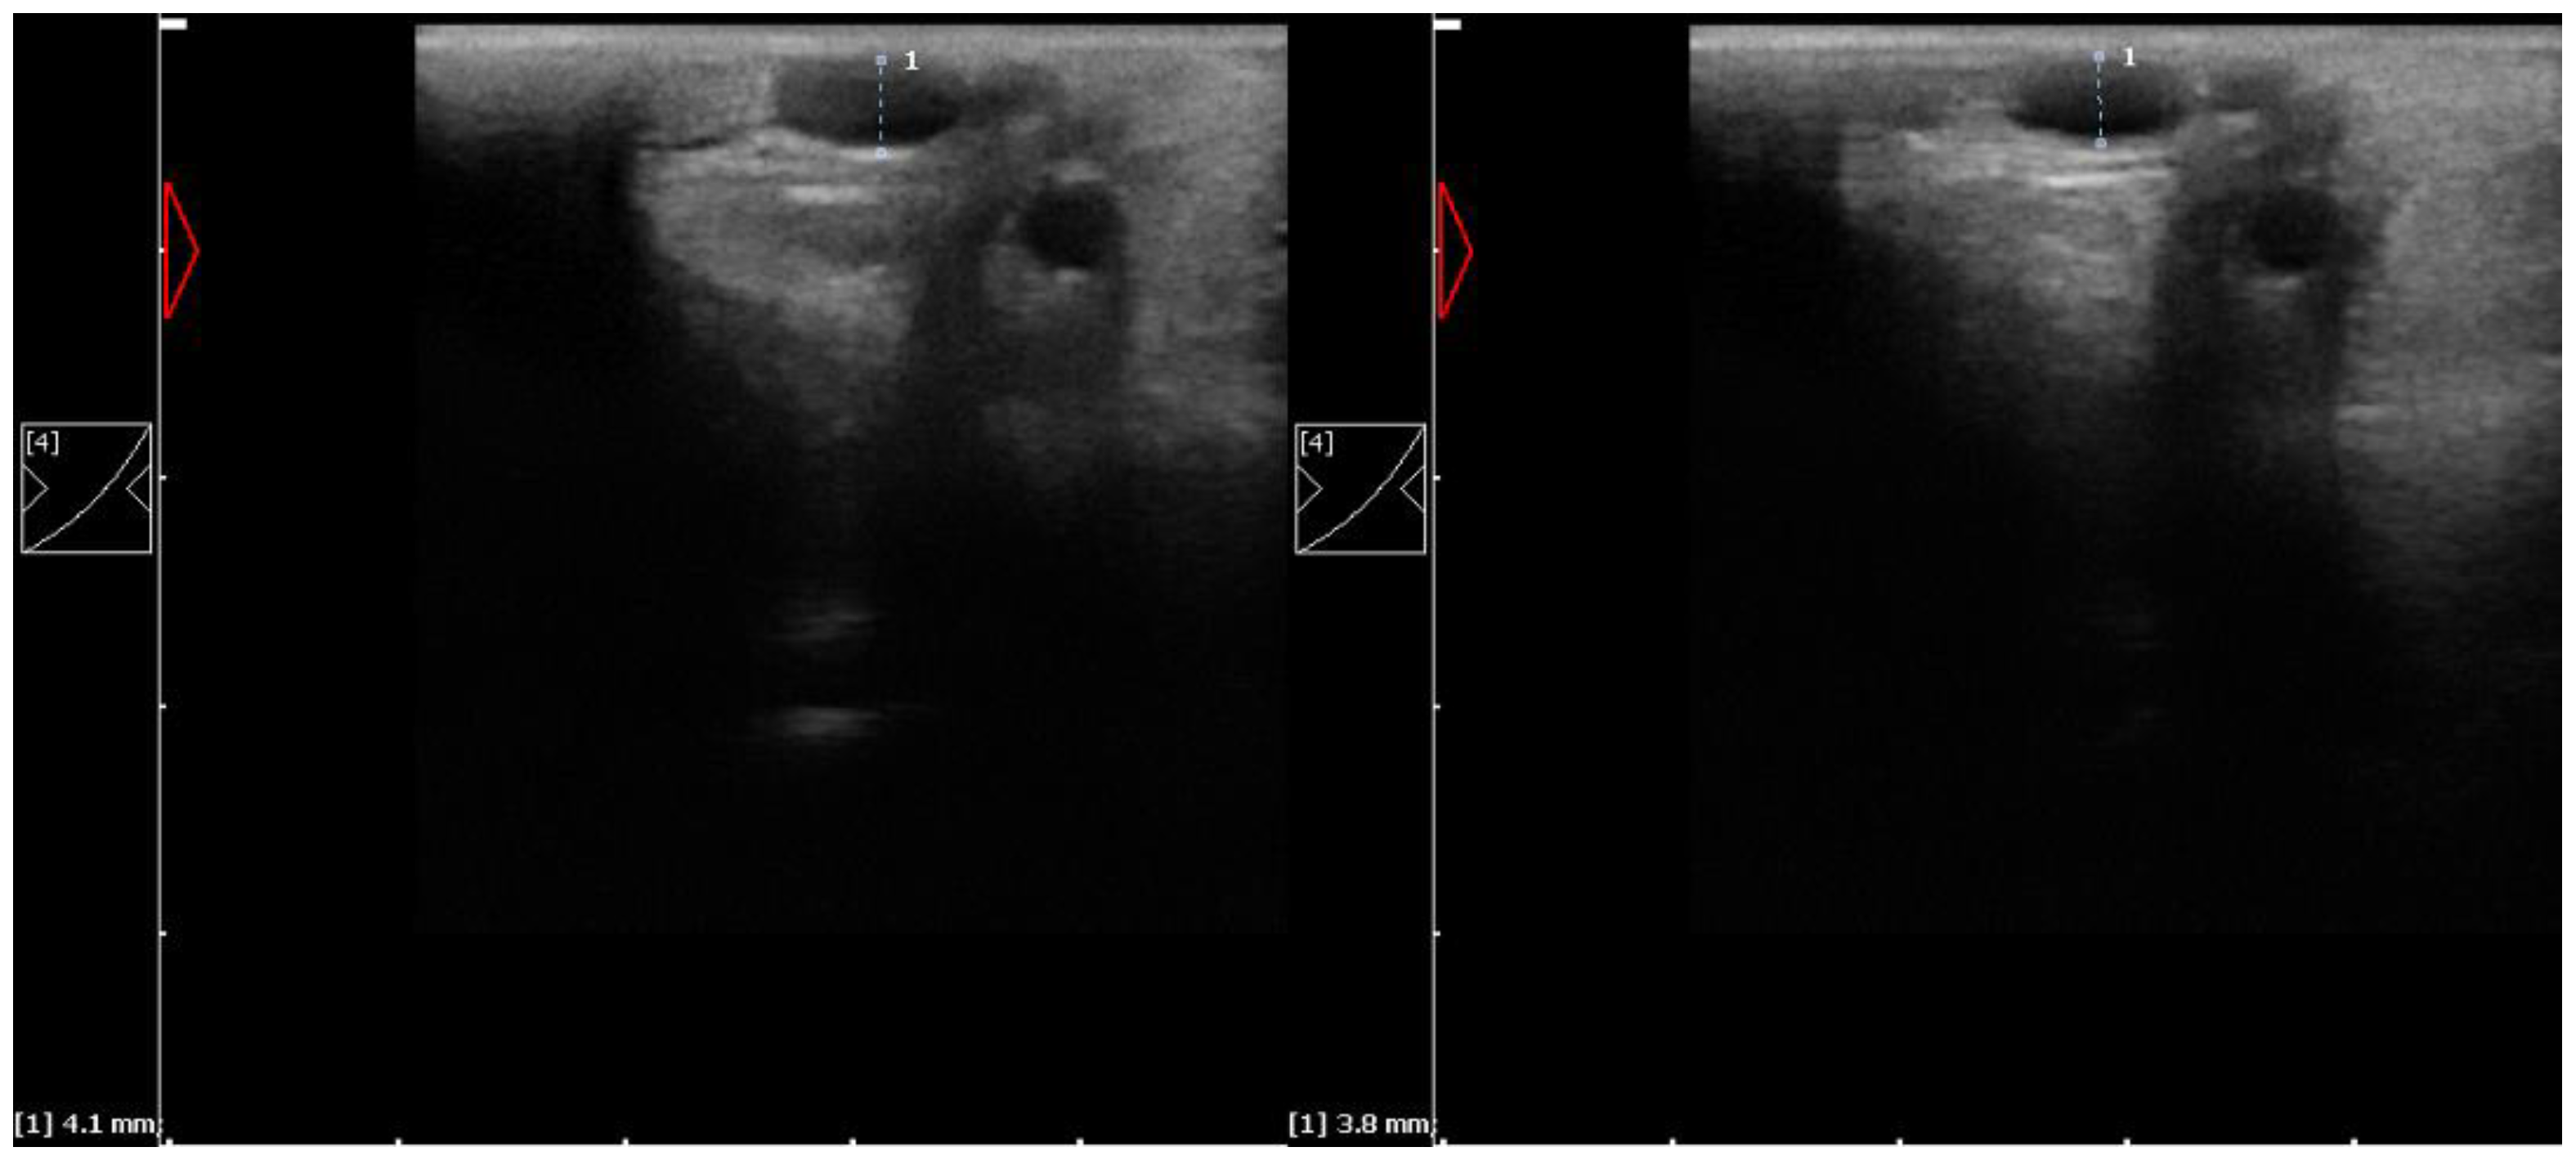

2.3. Ultrasonographic Examination

| D (mm) | 4.6 (4.0–4.9) | 4.6 (4.0–4.9) | 0.939 | 0.051 | |

| D (mm) | 5.3 (4.8–5.8) | 4.6 (4.2–5.1) | 0.130 | 0.796 | |

| ∆D (mm) | 0.8 (0.4–1.0) | 0.1 (0.0–0.2) | <0.001 *** | 0.999 | |